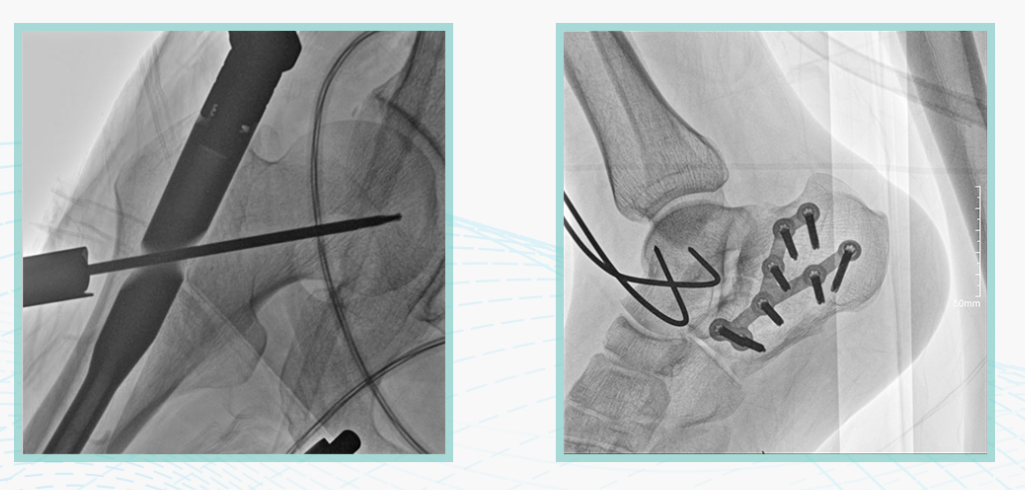

此外,骨科手術時間平均時長約為45分鐘左右時間,長期的X線透視或攝影曝光劑量將對臨床手術與操作醫務工作者造成難以評估的健康風險,悅畫通過支持攝影曝光參數的自主調節,可以保證在最低劑量水平下輸出滿足臨床手術定位與引導所需要的影像質量,相較于市面上的固定曝光參數配置移動C臂,自主參數調節設計的曝光功能設計,可以大幅減少醫務工作者的X線輻射劑量。

悅畫在影像的偽影處理上,也積累多項圖像處理專利技術。通過對植入物的精準識別,悅畫能夠精準祛除植入物偽影與運動偽影,保證高質量的影像輸出,無論是影像的對比度、分辨率(清晰度)相較于市面上的移動C臂產品都更勝一籌。